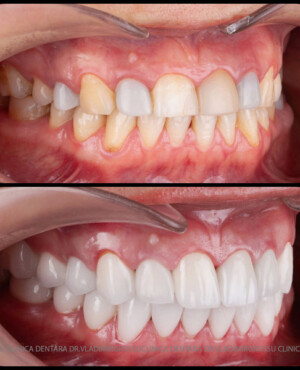

Cazuri clinice

Caz 1

Caz 2

Transformările estetice și impactul reabilitării asupra vieții pacienților

Reabilitarea dentară produce o schimbare vizibilă și profundă în aspectul pacientului, cu efecte pozitive evidente asupra stimei de sine și a calității vieții. Mulți pacienți relatează bucuria redobândirii funcției masticatorii și dispariția complexelor legate de aspectul dentar.